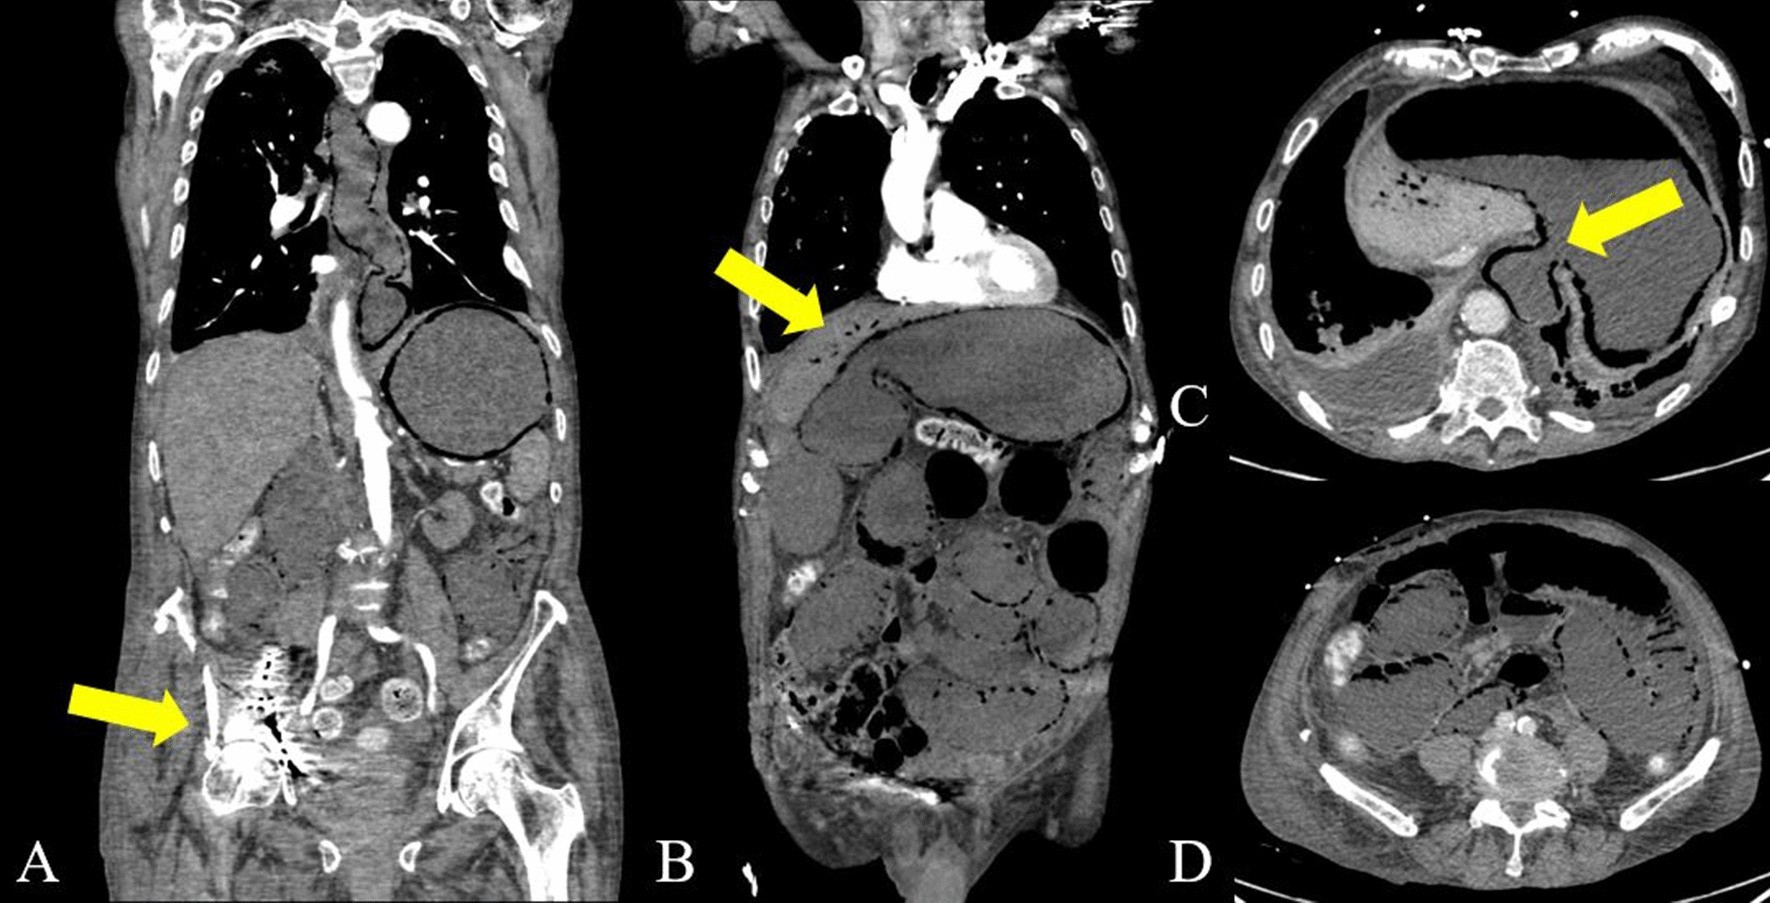

Fig. 6

From: Pneumatosis intestinalis and porto-mesenteric venous gas: a multicenter study

A-D is showing an arterial phase contrast enhanced CT with axial slices (A, B) and coronar reconstructions with a fulminant PI and PMVG (B, D) in a 85 year-old patient with sepsis. Note the presence of gas within in the intestinal wall the entire small and large intestine, as well as the oesophagus (C), caused by bacterial enteritis after surgical fixation of an acetabular hip fracture on the right (A) with pelvic perforation of the osteosynthesis. The patient died within 24 h after the CT-examination